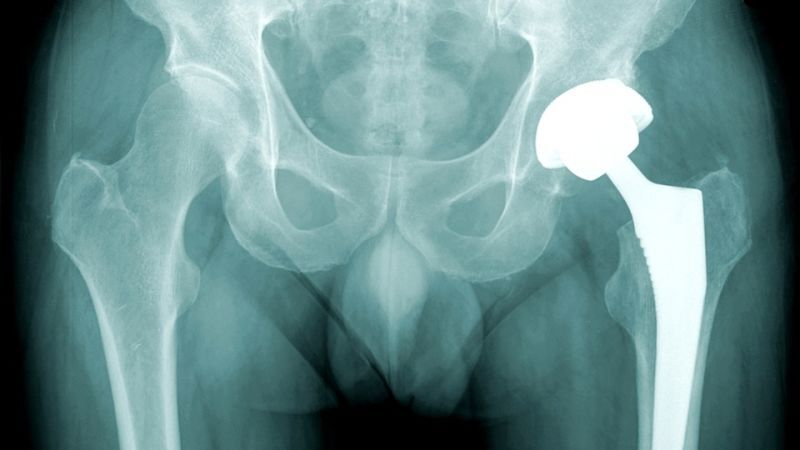

Alexander Selvik Wengshoel, the 25-year-old artist, was born with a deformed hip and spent years in a wheelchair while going through a series of failed operations. He was finally given his metal hip replacement when he was 21. His hip bone, which he was allowed to keep, was displayed alongside film of the operation as part of his graduation show from the Tromsø Academy of Contemporary Art. (He admitted that the project inspired "different reactions" at his college, saying, "Some like it, some understand, some hate it, some get really pissed off and start yelling at me ' this is not art.'")

[Image via Shutterstock, h/t NYDaily]